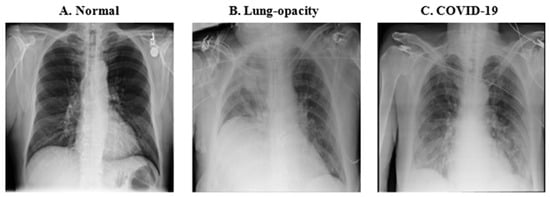

The most prevalent radiological manifestations of lung infection in individuals with COVID-19 consist of consolidations and ground-glass opacities. These radiographic features typically exhibit a bilateral distribution, with a predilection for the lower lobes and peripheral regions of the lungs. It is important to note that these findings, along with other patterns such as diffuse lung opacities, are not exclusively indicative of COVID-19 and can be present in other pulmonary conditions [35]. Chest X-rays offer a convenient, cost-effective, and rapid imaging modality for assessing individuals suspected of COVID-19 infection, with portable X-ray machines being widely employed in such scenarios. Figure 1 provides a visual comparison of chest X-rays depicting a healthy individual and a COVID-19 patient with evident lung opacity.

Figure 1. Chest X-ray figures used for the training. (A). (Normal fig.) A normal chest X-ray of a healthy individual. (B). (Lung-opacity fig.) A patient with unilateral right-sided opacity from another cause. (C). (COVID-19 fig.) A COVID-19 patient with bilateral opacities consistent with COVID-19 pneumonia.